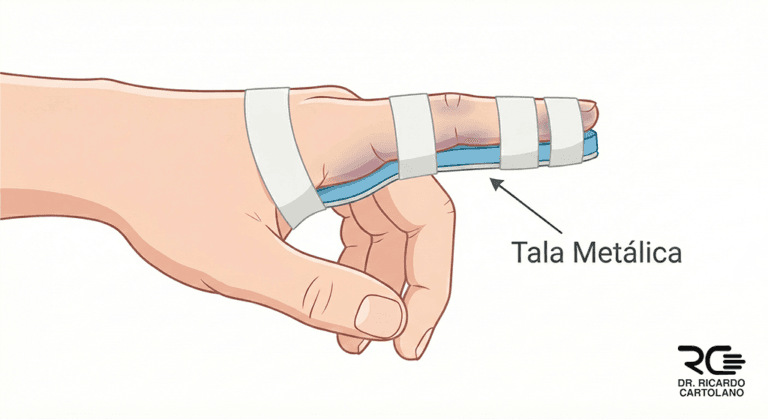

Muitas fraturas dos dedos podem ser tratadas sem cirurgia (tratamento conservador), especialmente se estiverem estáveis e bem alinhadas. As opções incluem:

Imobilização com “Buddy Taping”: É a técnica de prender o dedo fraturado ao dedo saudável ao lado com uma fita (esparadrapo). O dedo saudável serve como uma “tala” móvel.

Talas (Órteses): Pequenas talas de plástico, metal ou gesso podem ser usadas para proteger o dedo e mantê-lo na posição correta por algumas semanas (geralmente de 3 a 4).

Durante esse período, o médico pode indicar o início precoce de movimentos leves para evitar que os tendões “grudem”.